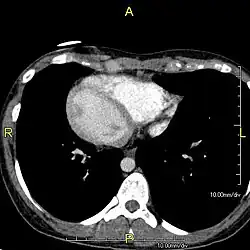

Situs inversus is found in about 0.01% of the population, or about 1 person in 10,000. In the most common situation, situs inversus totalis, it involves complete transposition (right to left reversal) of all of the viscera. The heart is not in its usual position in the left chest, but is on the right, a condition known as dextrocardia (lit. 'right-hearted'). Because the relationship between the organs is not changed, most people with situs inversus have no associated medical symptoms or complications.[1]

The condition affects all major structures within the thorax and abdomen. Generally, the organs are simply transposed through the sagittal plane. The heart is located on the right side of the thorax, the stomach and spleen on the right side of the abdomen and the liver and gall bladder on the left side. The heart's normal right atrium occurs on the left, and the left atrium is on the right. The lung anatomy is reversed and the left lung has three lobes while the right lung has two lobes. The intestines and other internal structures are also reversed from the normal, and the blood vessels, nerves, and lymphatics are also transposed.

If the heart is swapped to the right side of the thorax, it is known as "situs inversus with dextrocardia" or "situs inversus totalis". If the heart remains on the normal left side of the thorax, a much rarer condition (1 in 2,000,000 of the general population), it is known as "situs inversus with levocardia" or "situs inversus incompletus".

Diagnosis of situs inversus can be made using imaging techniques such as x-ray, ultrasound, CT scan, and magnetic resonance imaging (MRI).[9]